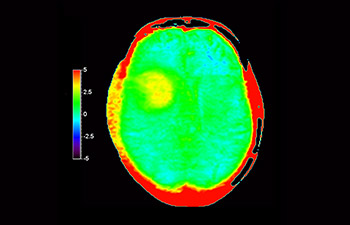

3D APT (Amide Proton Transfer) is a unique, contrast-free, brain MR imaging method addressing the need for more confident diagnosis in neuro oncology. 3D APT uses the presence of endogenous cellular proteins, to produce an MR signal that directly correlates with cell proliferation, a marker of tumoral activity. 3D APT can support trained medical professionals in differentiating low grade from high grade gliomas and, in differentiating tumor progression from treatment effect1.

Astrocytoma

Brain astrocytoma, post-radiotherapy

with 3D APT